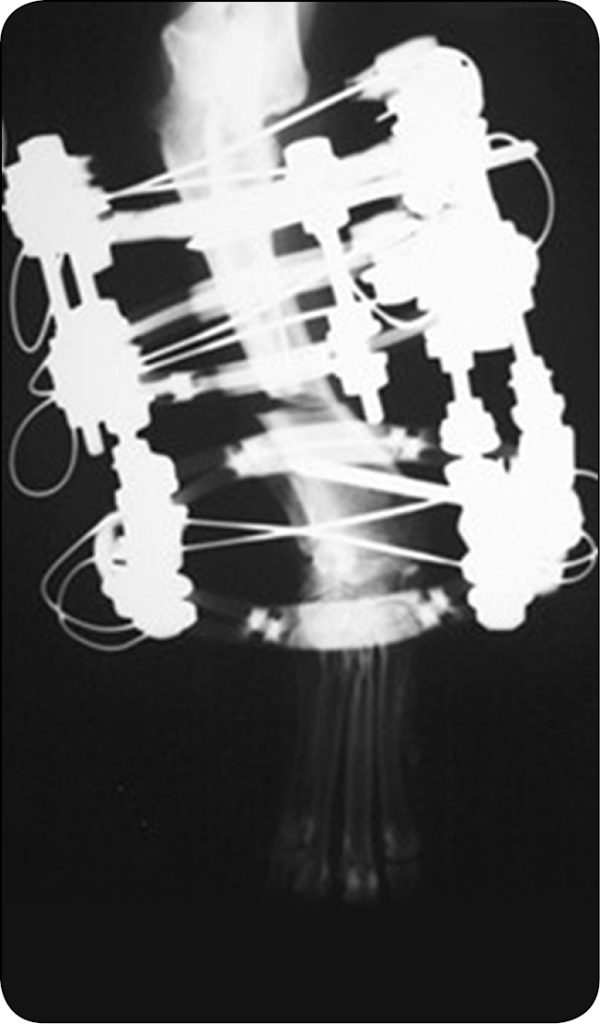

Osteotomię wykonywano piłą oscylacyjną lub osteotomem, zależnie od preferencji chirurga. Deformację skrętną korygowano bezpośrednio o wartość ustaloną podczas planowania przedoperacyjnego (ryc. 3a-b). W tym celu zawiasy odłączano od bloku dystalnego, kikut dystalny obracano o żądaną wartość, a następnie zawiasy ponownie łączono z blokiem dystalnym we wcześniej obliczonej pozycji.

Ponieważ blok dystalny został przekręcony, punkty połączeń zawiasów z blokiem dystalnym różniły się od tych przed wykonaniem obrotu (ryc. 4a-b).